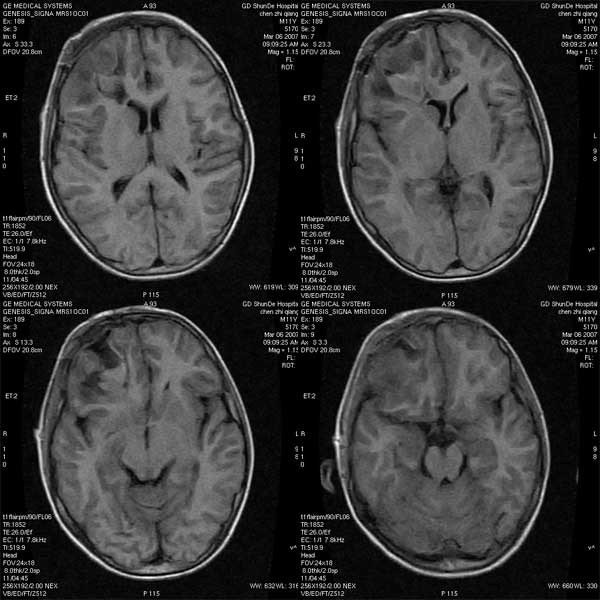

性别:m

年龄:11

病历摘要:右颞开放性颅脑损伤治疗后复查